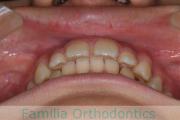

No.23V-385

- 主な症状:

- 叢生

- 年齢:

- 17歳

- 性別:

- 女性

- 抜歯部位

- 上:

- 44

- 下:

- 8448

- 主な使用装置:

- FEA 022

- 治療にかかった費用:

- 90万円

前歯のゆがみ、ズレがあるのを治したいということで来院されました。上下左右から小臼歯を抜歯して、マルチブラケット法にて治療をしました。1年8か月、20回程度の通院をしていただきました。叢生(でこぼこ、凹凸、ガタガタ)が強いため、保定をしっかりしないと後戻りのリスクがやや高いケースといえます。

- ≫治療前

-

上顎

下顎

前歯の関係など